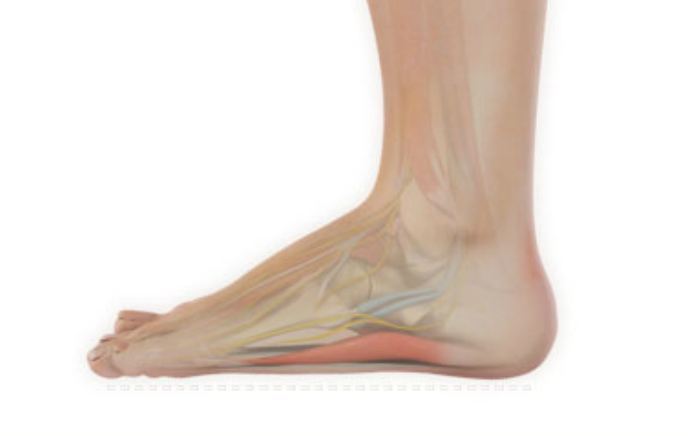

Common Foot & Ankle Disorders

Did you know the foot has 26 bones, 33 joints, 107 ligaments, 19 muscles, and numerous tendons? These parts all work together to allow the foot to move in a variety of ways while balancing your weight and propelling you forward or backward on even or uneven surfaces. It is no wonder that 75 percent of all Americans will experience foot problems at one point or another in their lifetimes.